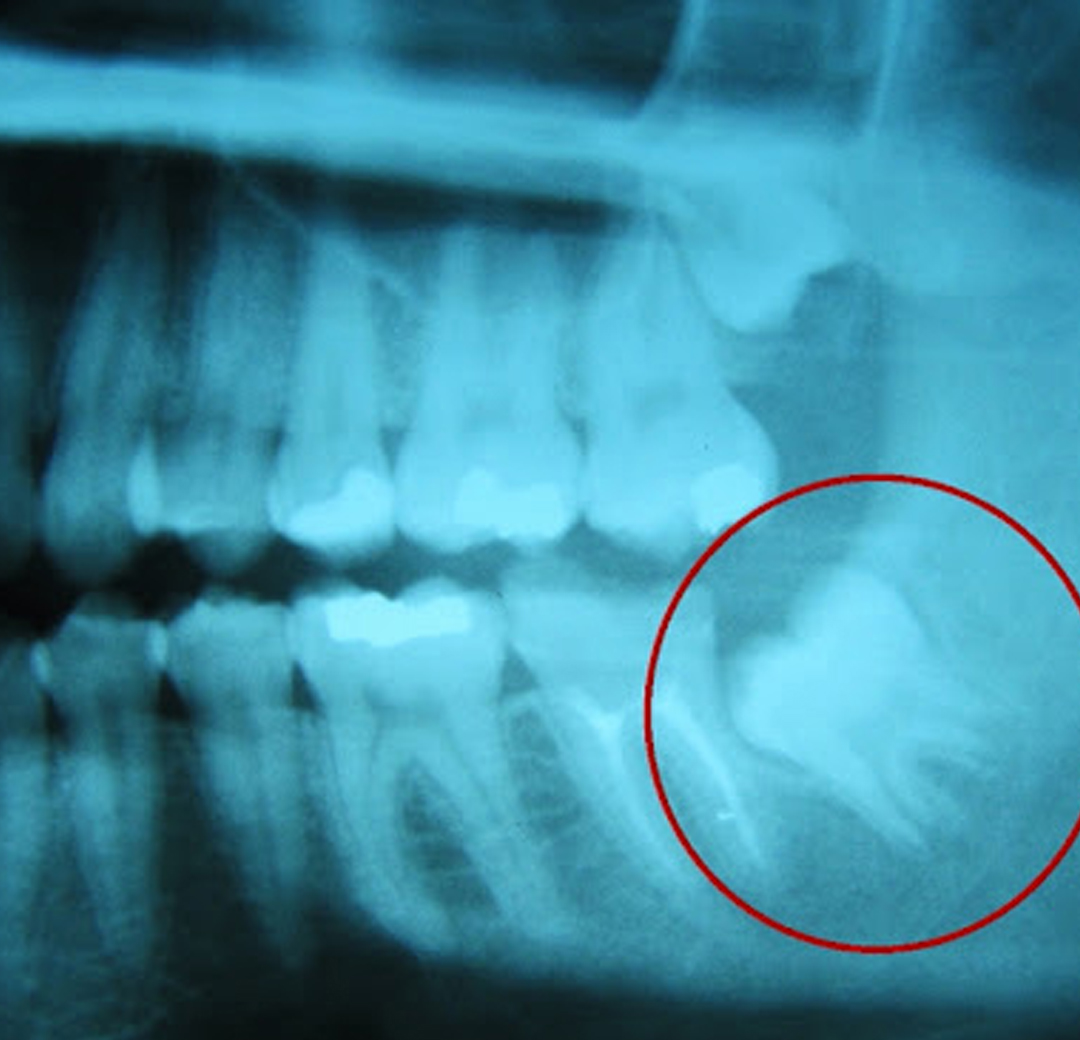

Os terceiros molares, conhecidos como dentes sisos, são os últimos dentes da boca. E correspondem a quatro dentes no total, dois superiores e dois inferiores. A extração do dente siso pode ou não ser necessária.

A extração do dente siso é indicada em algumas situações, dentre elas temos a falta de espaço na arcada, questões protéticas e/ou ortodônticas, presença de infecção em uma maior porção do dente ou do osso ao redor, lesões cariosas devido a incapacidade de uma higiene adequada, entre outros fatores.

Sim. Como são os últimos dentes a nascer, pode ser que os mesmos não encontrem espaço suficiente na boca. Dessa forma, essa falta de espaço pode acarretar uma movimentação dos outros dentes, provocando assim um desalinhamento, que além de atrapalhar a estética, dificulta a higienização.